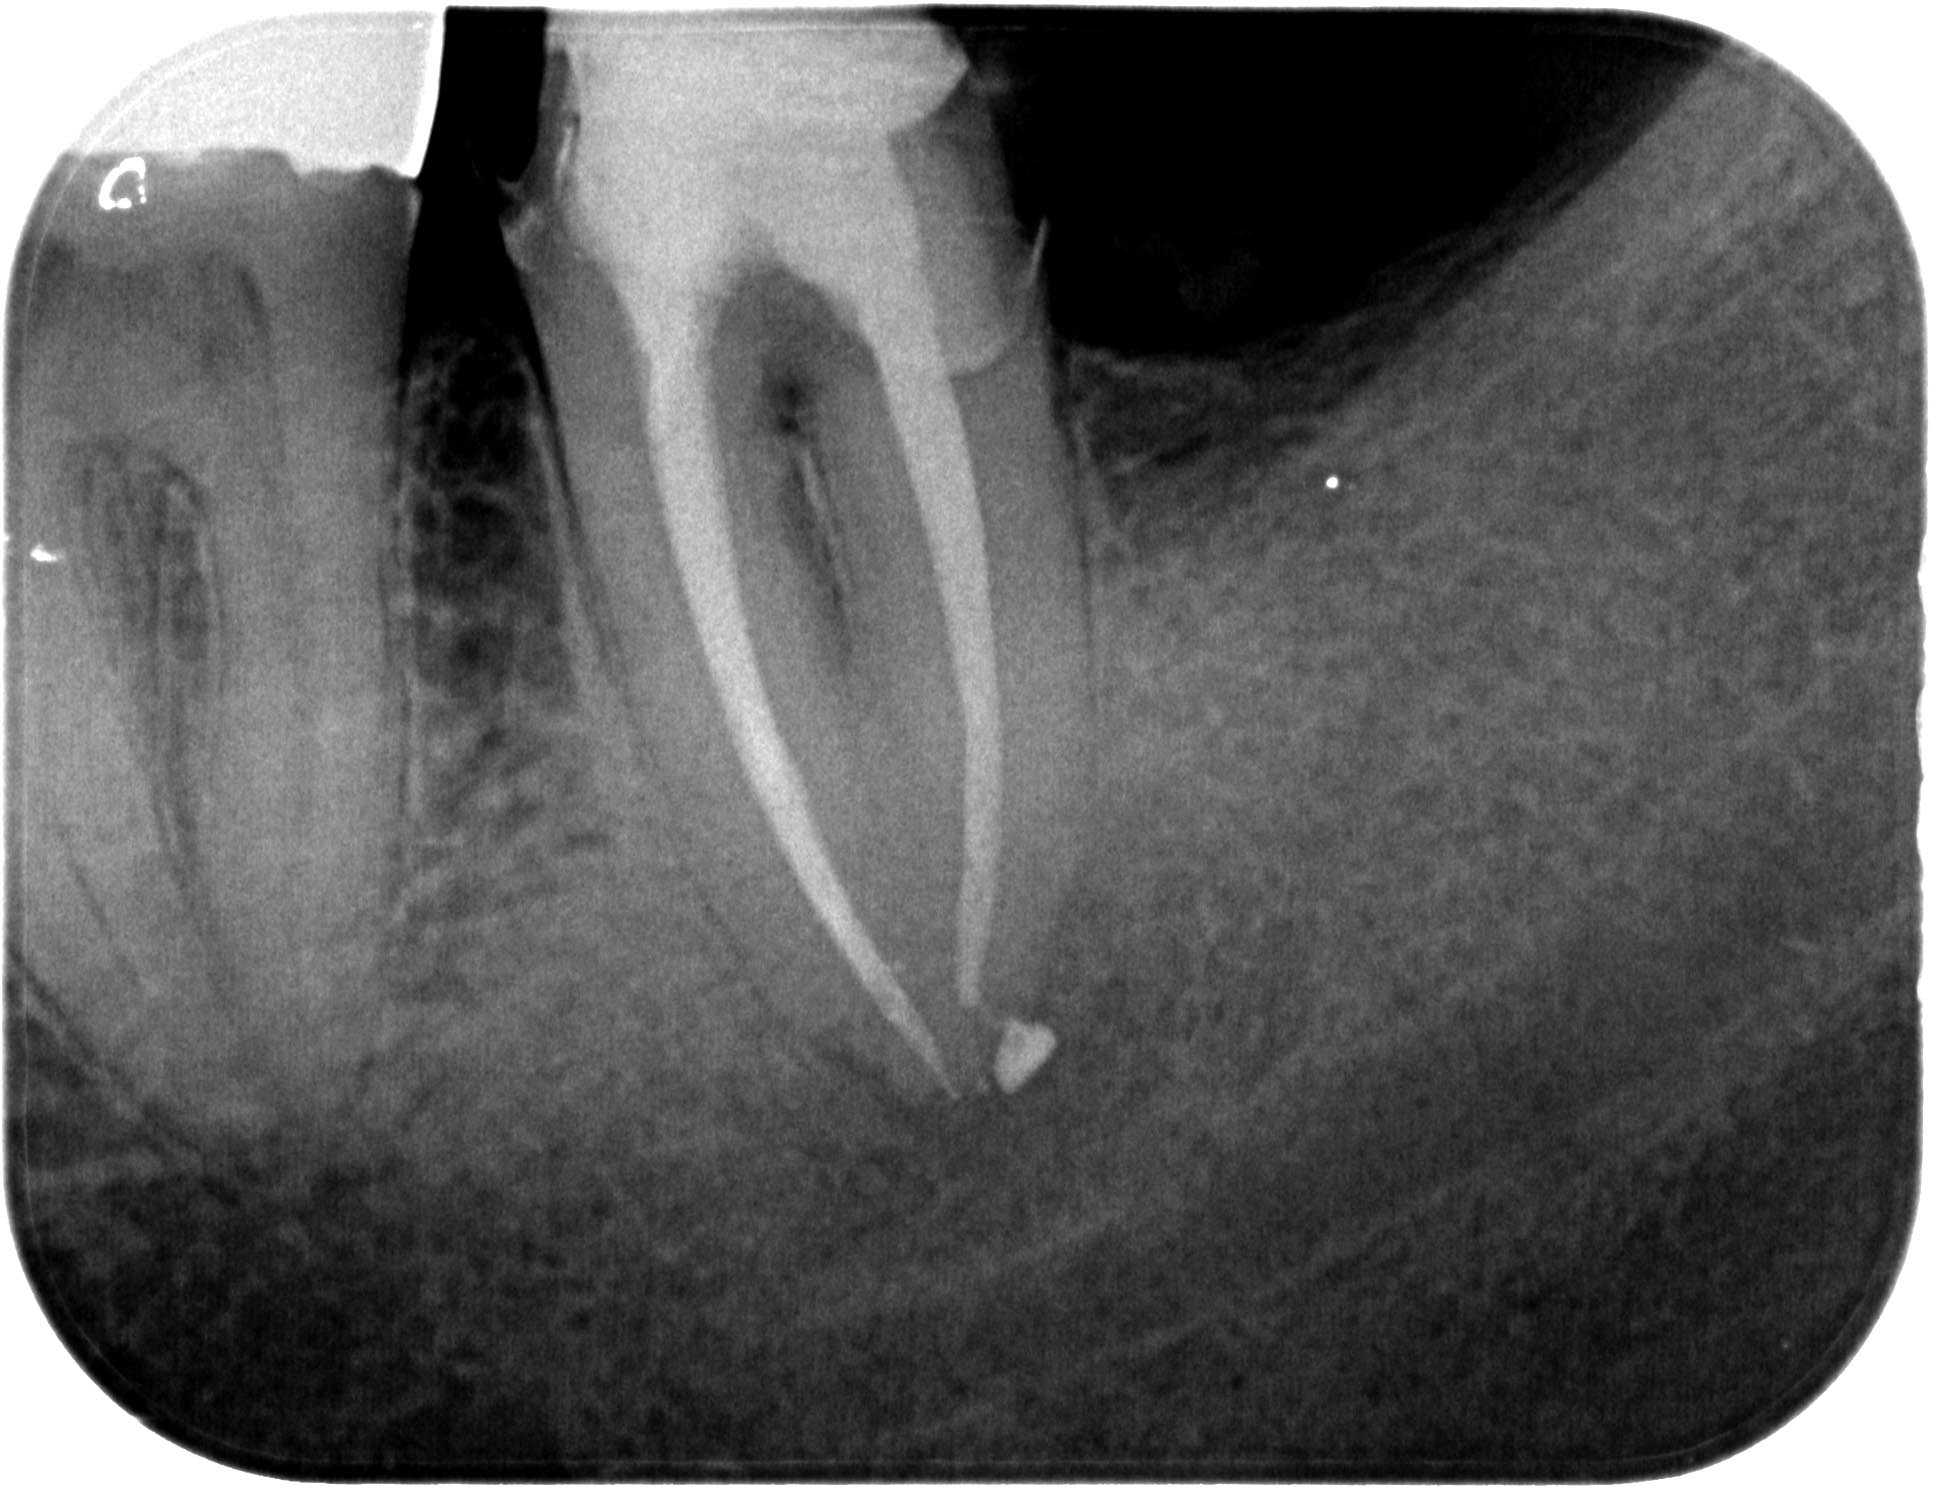

KSKrone6MonatepostWF-1-4 Veröffentlicht 24. September 2015 am 1933 × 1487 in Zuverlässige Endometrie bei Metallkronen – aber auch – Wäre das nicht eine sinnvolle neue Rubrik für WURZELSPITZE ? Zahn 37 6 Monate post WF